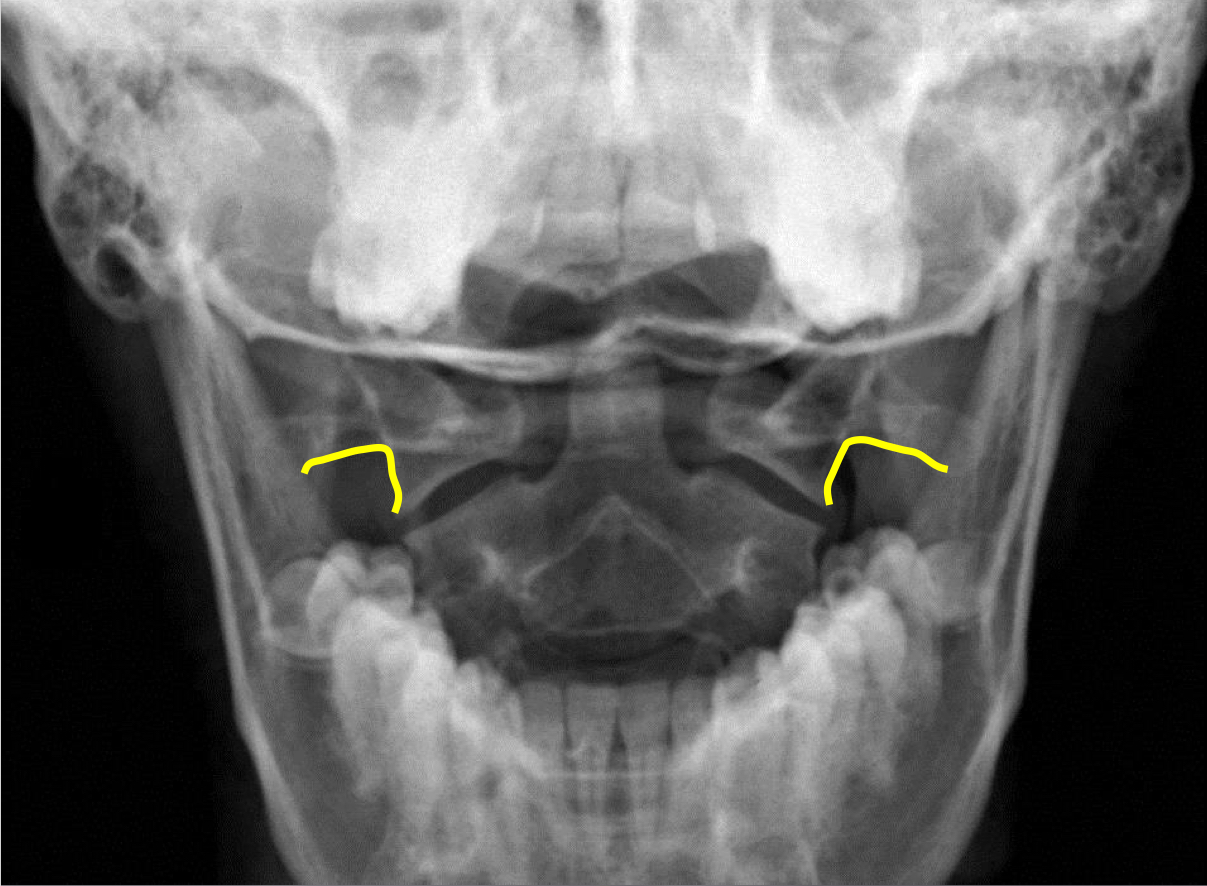

What view is this?

APOM

What is this?

C1 Lateral Masses

What is this?

Mastoid Processes

What is this - Yellow?

Occipital Condyles

What is this - blue?

Foramen Magnum

What is this?

C1 TVP/Lateral Mass Junction

What is this?

Odontoid Process

What is this?

C2 Spinous Process

What is this?

C2 Pedicle Shadows